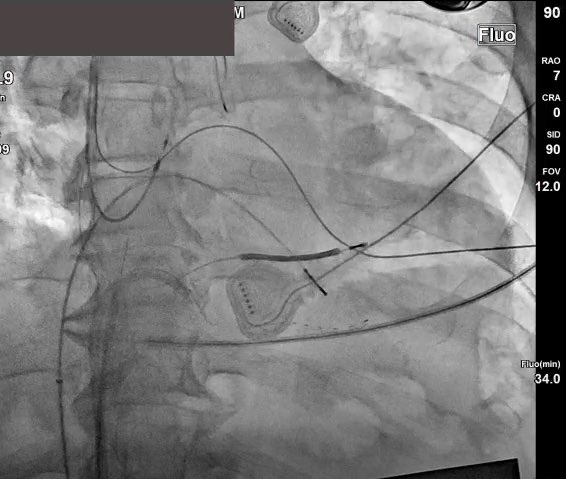

In the lab with @docAnneSquared today so you know it’s gonna be good! Shown here RV apical and RVOT pacing open window mapping helping us find this beautiful slanted pathway. One burn to cure! ❤️🔥 Thanks to the OG of mapping @AMatthews0 for these beautiful maps. @MUSC_EP